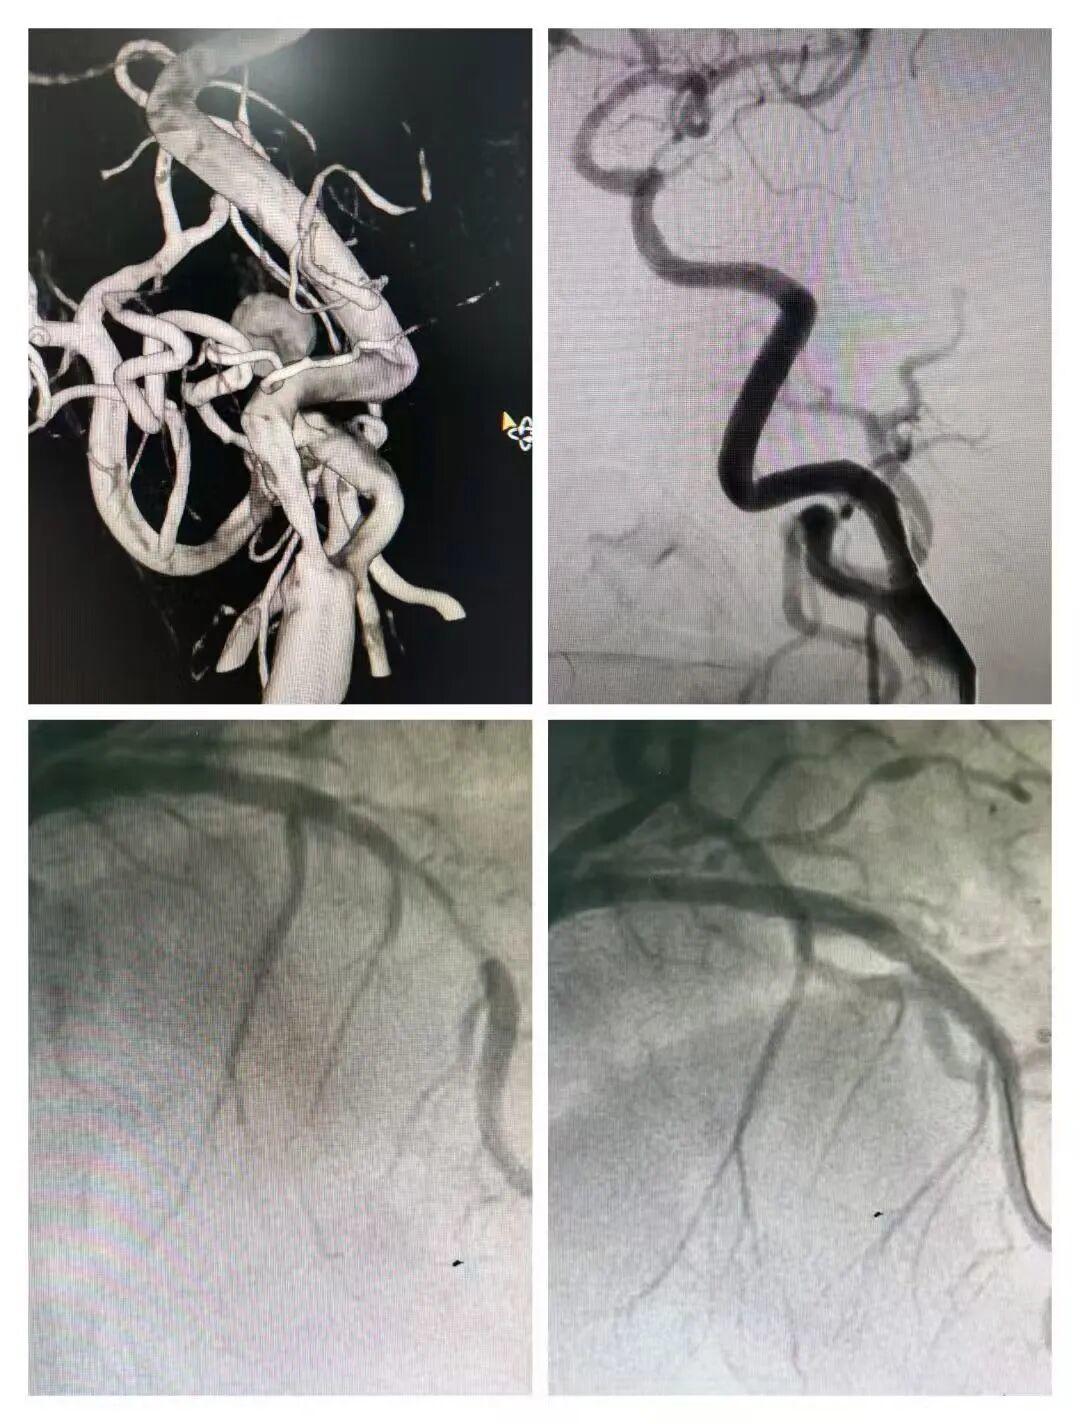

68岁的孙先生是在青岛心血管病医院接受过心脑联合治疗的一位患者。他因脑梗复发伴胸前区疼痛就诊,神经科介入团队姜绪涛主任完善检查后发现,其同时存在冠状动脉与颈动脉重度狭窄,病情凶险。神经科与心内科团队紧急联合会诊,结合患者年龄、病情及家属意愿,决定同期介入处理两处病变,降低手术风险。术中,姜绪涛主任首先实施颈动脉支架植入术,精准释放保护伞并植入支架,有效扩张狭窄斑块,解除脑部供血危机。随后,心内科介入团队接力完成冠脉支架植入,疏通狭窄冠脉。整场手术衔接流畅,一次手术、一次住院,成功解除患者双重病痛。

“心脑同治”的核心,在于打破学科壁垒,实现心血管与神经系统诊疗的深度协同、优势互补。医院将这一核心理念深度融入临床实践,针对同时存在严重冠状动脉狭窄与脑血管严重狭窄或闭塞的患者,心内科与神经介入专家依托先进的影像融合技术,共同细致评估病变性质、位置、风险等级及手术先后顺序,综合考量患者心脏泵血功能、脑血管侧支循环、手术耐受度等关键因素,为每位患者量身定制最优个体化联合手术策略,确保手术安全、高效、精准。